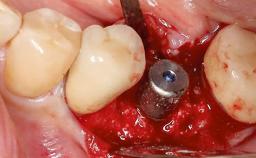

Open-Flap Debridement for the Management of Peri-Implant Mucositis Associated with Excess Cement

A 79-year-old female patient was referred to the Department of Periodontology of the University of Bern, Switzerland by her private dentist in May 2019. She had been rehabilitated in May 2005 with two tissue-level implants (Institut Straumann AG, Basel Switzerland) at sites 13 and 15, supporting a three-unit cemented fixed dental prosthesis (FDP). The metal-ceramic FDP had been cemented permanently with a glass-ionomer cement (Ketac Cem; 3M ESPE, Seefeld, Germany). Implant 13 had been diagnosed with peri-implant mucositis by the referring dentist in the course of regular supportive therapy. The patient was in good general health, did not smoke, and exhibited good self-performed plaque control.